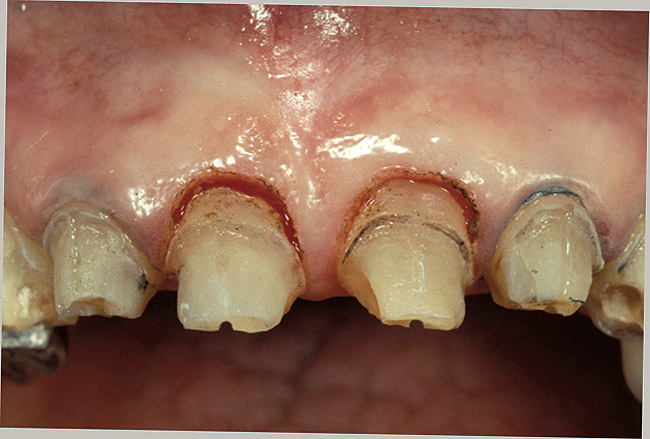

Clinical Procedures in Margin Placement

The placement of supragingival or equigingival margins is simple because they require no tissue manipulation. Regarding overall tooth preparation, the amount reduced incisally or occlusally, facially, lingually, and interproximally will be dictated by the choice of restorative materials. Before extending subgingivally, prepare every tooth right to the free gingival margin facially and interproximally. This allows the margin of the tooth preparation to be used asa reference for subgingival extension once the tissue is retracted (Figures 13, Figure 14, Figure 15 and Figure 16).

Figure 13  A patient who will require the removal of the left lateral incisor because of a split root. Due to the poor condition of the existing teeth, a bridge will be placed from the right central to the left cuspid. The patient declined an implant and is concerned about future recession.

Figure 13

Figure 14  Very dark roots and 3 mm of sulcus depth make the possibility of recession a concern. On the incisors, the decision was made to perform a gingivectomy and create a 1-mm sulcus, followed by placing the margins 0.5 mm below tissue. On the canine a gingivectomy would result in an excessively long tooth compared to the opposite canine, so the decision was made to prepare one-half the depth of the 3-mm sulcus below tissue and hope for no recession. If any occurs, the margin should remain below tissue.

Figure 14

Figure 15  The gingivectomy on the incisors was performed, leaving a 1-mm sulcus depth.

Figure 15

Figure 16  The first step in controlling margin placement is to prepare the tooth even with the gingival margin.

Figure 16